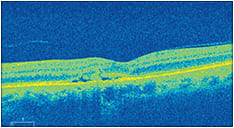

Slit lamp examination showed no evidence of inflammation in the anterior or posterior chamber OU. Dilated evaluation revealed retinal pigmentary changes and a 2 disc-diameter, well-circumscribed collection of subretinal fluid with multiple “yellow” dot-like precipitates inferior to the macula OS. OCT showed a neurosensory ret-inal detachment with evidence of a choroidal neovascular membrane (CNVM) OS. No abnormalities or drusen formation were observed in the fellow eye.

An OCT image revealed a neurosensory retinal detachment with evidence of a choroidal neovascular membrane OS.

• SD-OCT. This allows for the evaluation of CSCR clinical signs, including neurosensory or subretinal fluid, intraretinal cystic changes, diffuse RPE loss and thinning/discontinuity of the inner segment/outer segment line. Hyperflective dots, which represent phagocytosed photoreceptor outer segments and thickened choroid in the areas corresponding to the neurosensory detachment, can also be observed.